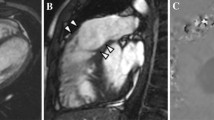

CMR is the investigation of choice for the evaluation of repaired TOF and DORV. Residual RVOT stenosis (the commonest late complication post-infundibulectomy) is diagnosed in suspected cases by visualising the narrowing of RVOT (which persists even during diastole) [23]. CMR can help in its quantification. Right ventricular outflow patch dyskinesia/aneurysm can occur secondary to RV dysfunction. Varying degree of tricuspid regurgitation (TR) is associated with the obligatory PR in patients after transannular patch repair (Figs. 18.17 and 18.18). Recurrent/residual ventricular septal defect also requires MR quantification of Qp/Qs which is not possible on CTA. Also, small defects in distorted post-operative anatomies are better imaged on CMR. Progressive left ventricular dysfunction is a poor prognostic marker in these patients. This is assessed best on CMR, including subclinical dysfunction utilising tagging and strain imaging. A myocardial infarction secondary to vascular injury is visualised on CMR, though the anomalous course of coronary and its relationship to surrounding structures is best diagnosed on CTA.

Same case as Fig. 18.17—CMR phase-sensitive inversion recovery images show late gadolinium enhancement in the right ventricle (RV) and right ventricular outflow tract outpouching (*)

Regarding PR, there are definite CMR criteria for decision-making for pulmonary valve replacement [24] (Fig. 18.19).